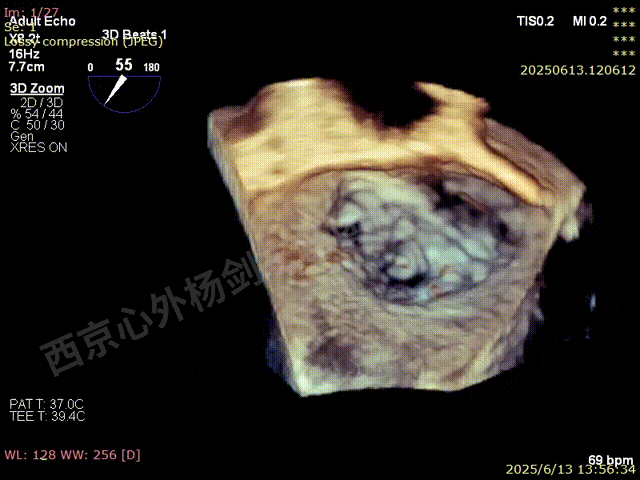

术前3D数字模型

图片